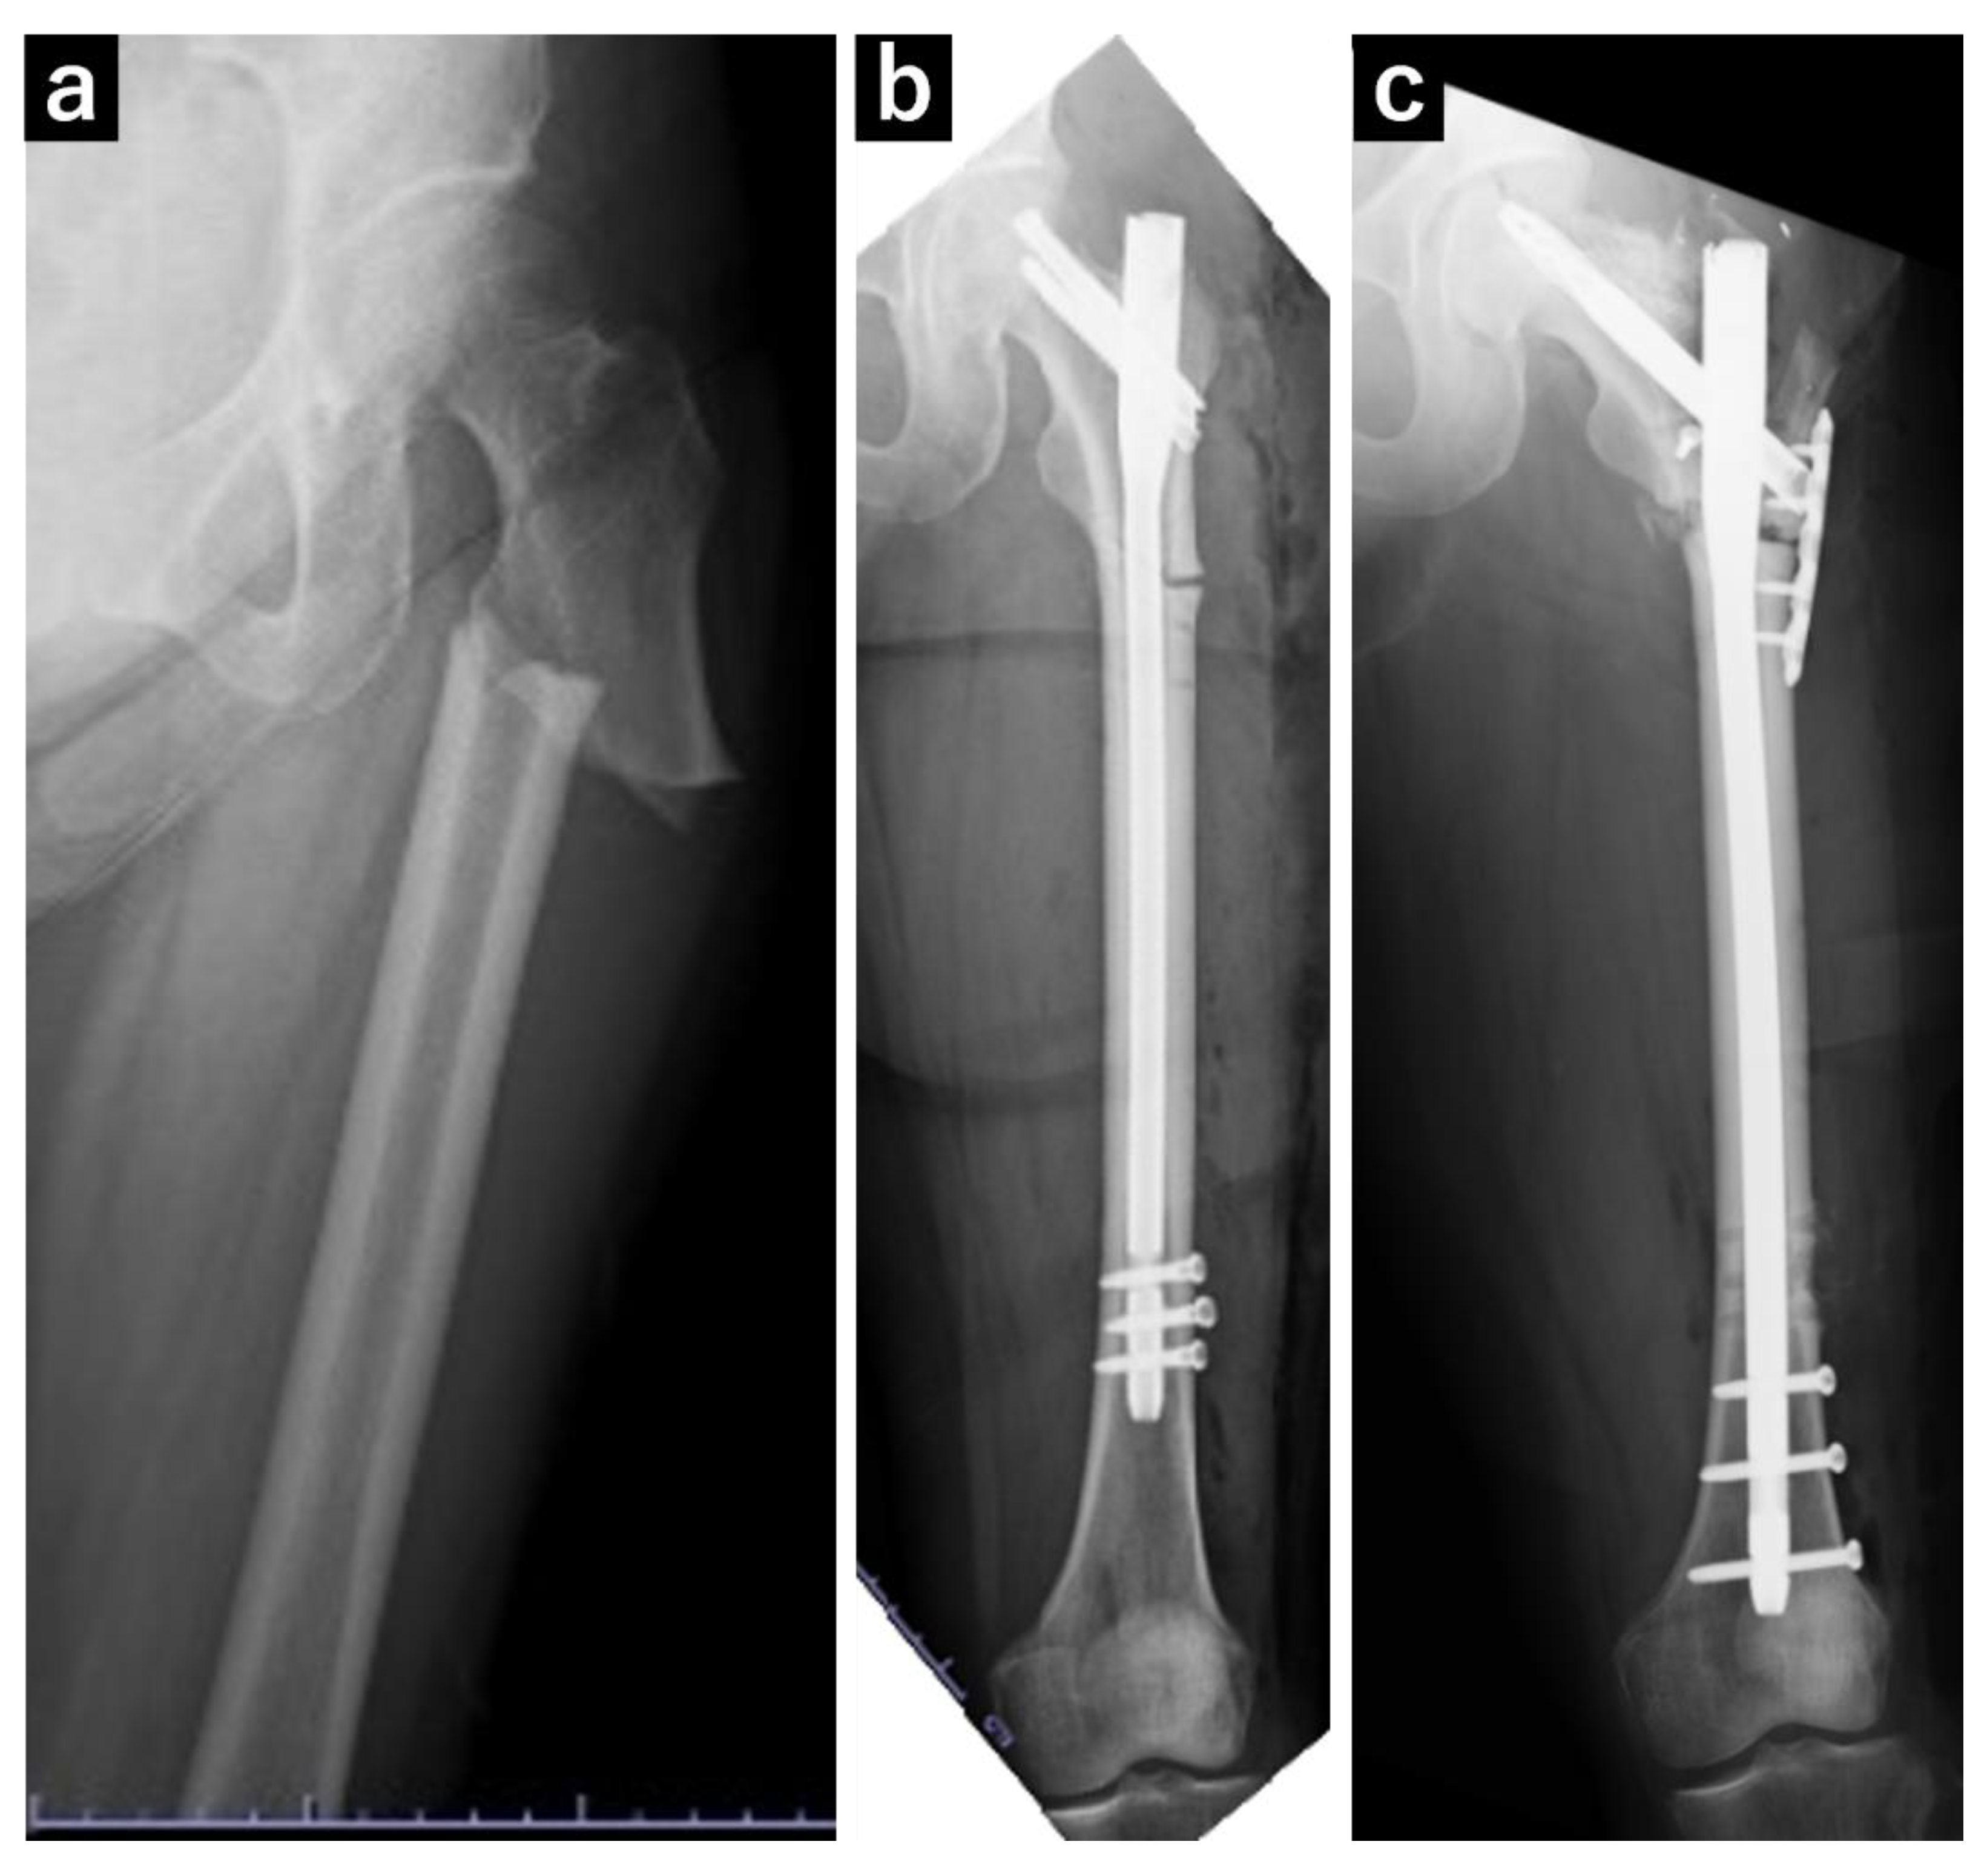

At 73 years of age, the patient experienced a fall and was diagnosed with a left subtrochanteric AFF based on plain radiography and computed tomography (CT) findings. Additionally, localized lateral cortical thickening was observed in the ipsilateral subtroschanteric region, along with osteoarthritis of the right hip (Figure 1). The patient underwent open reduction and internal fixation with an intramedullary nail for the left subtrochanteric AFF. Alendronate was discontinued, and treatment comprising 600 µg teriparatide (recombinant) was initiated, which was continued for 2 years. Due to nonunion at the fracture site, the patient underwent surgery for pseudarthrosis at 75 years of age (Figure 2). Given the gradual worsening of the right hip osteoarthritis, THA was planned when the patient turned 78 years of age.

Figure 1. Plain radiograph of the left femur. (a) A transversal fracture in the subtrochanteric region of the left femur diagnosed as an atypical femoral fracture. (b) Postoperative image following open reduction and internal fixation of the atypical femoral fracture. (c) Postoperative image following surgery for pseudarthrosis of the left femur, in which replacement with a long nail and additional plate fixation were performed.